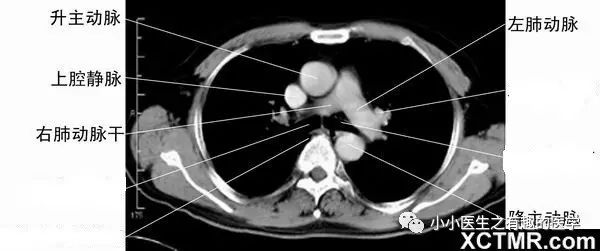

10.一定要知道肺动脉,因为肺动脉栓塞很危险,另外,正常情况下肺动脉比主动脉小,假如肺动脉比主动脉宽,sorry,可能患肺动脉高压了。

最大的,一升一降,分别为升主动脉、降主动脉。人字形的肺动脉,剩下的为上腔静脉。